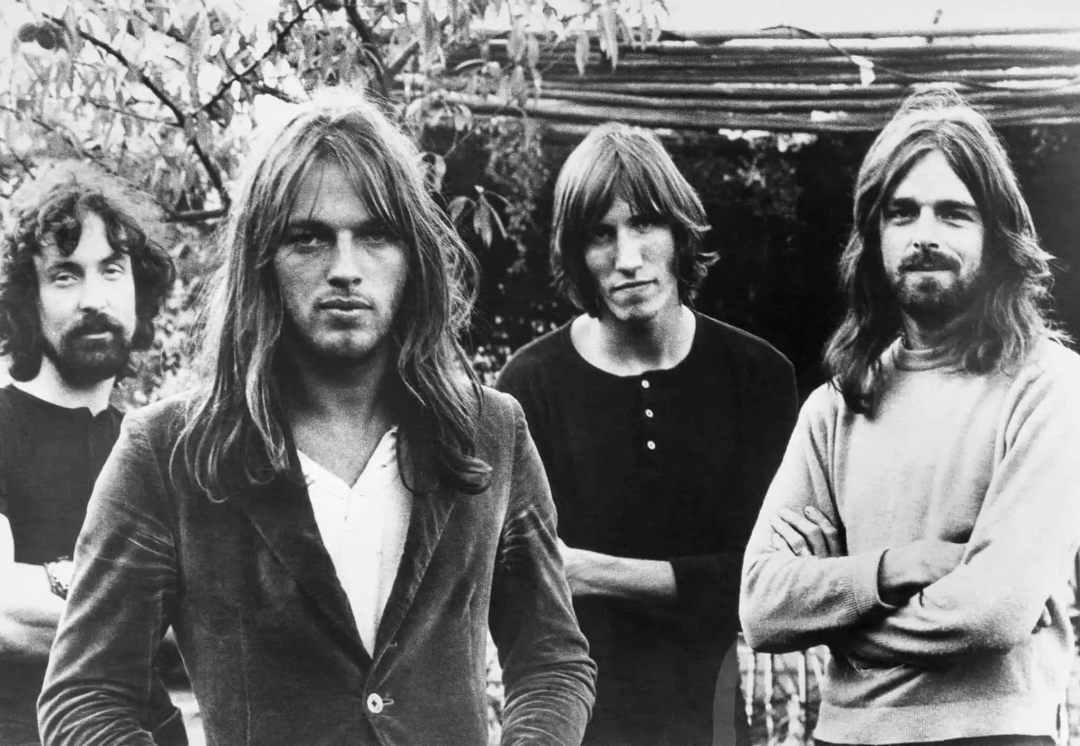

将原始歌曲波形转换为仅有幅度的听觉频谱图,然后使用迭代相位估计算法将其转换回波形。

该研究涉及29例接受颅内脑电图(iEEG)治疗癫痫的患者。在手术过程中,患者听着平克·弗洛伊德的流行歌曲,同时记录下他们的神经活动。然后,研究人员使用了一种所谓的刺激重建方法,看看他们能否仅通过神经活动就能重放原来的歌曲。

为此,研究人员训练了一种机器学习算法,以识别与歌曲的不同方面(如旋律、节奏和歌词)相对应的神经活动模式。重建后的歌曲并不是原版歌曲的完美复制品,但可以清晰辨认,并包含歌曲的许多关键元素,如旋律、节奏和歌词。这几乎就像是病人在脑海中哼唱歌曲的旋律,而研究人员可以从曲调中获取灵感。

协议、数据准备和编码模型拟合 Credit: PLOS Biology, Knight et al.

"我们能从头皮脑电图中获得的主要是包络线,从而了解歌曲的节奏模式。如果我们对其进行重建,这足以识别出著名的音乐作品。"Ludovic 说:"换句话说,在足够长的神经记录时间内,计算机可以识别它,但人很可能无法识别。"